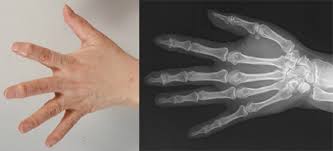

후기 단계

손가락 관절염이 심해지면 관절의 형태가 변형되기 시작합니다. 손가락의 외관이 변하고, 관절이 비정상적인 방향으로 굽히거나 마디가 돌출될 수 있습니다. 이러한 후기 단계의 변형은 손의 기능을 크게 제한하며, 일상생활에서 큰 불편을 초래합니다.